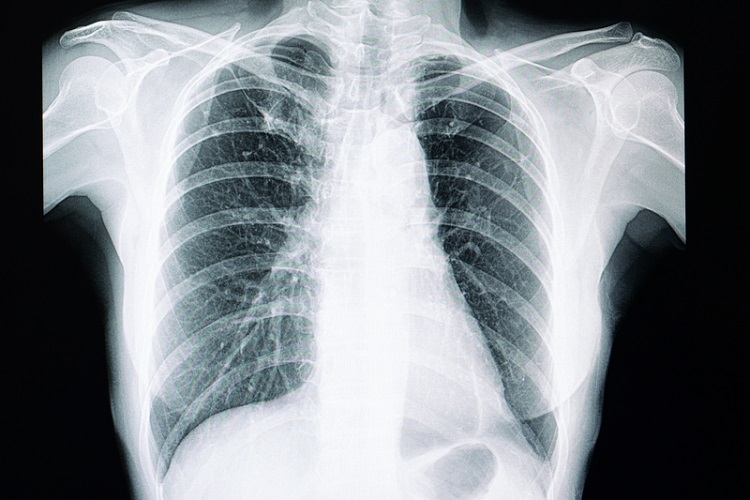

统计局数据显示,肺炎是2024年我国华人群体的主要死因,同时也是全国女性的首要死因之一。去年全国共有6776名女性因肺炎离世,占女性经医学确认死亡案例的12.4%。

数据指出,肺炎亦是我国第二大死因。2024年全国共录得1万5332宗肺炎死亡个案,占经医学确认死亡总数的11.5%。其中,华人占12.7%或4231宗,为各族群中比例偏高者。

统计局说明,肺炎死亡人数居高,可能与冠病疫情后阶段有关,社区肺部感染病例增加,尤其对免疫力较弱或患有慢性疾病者影响更为明显。